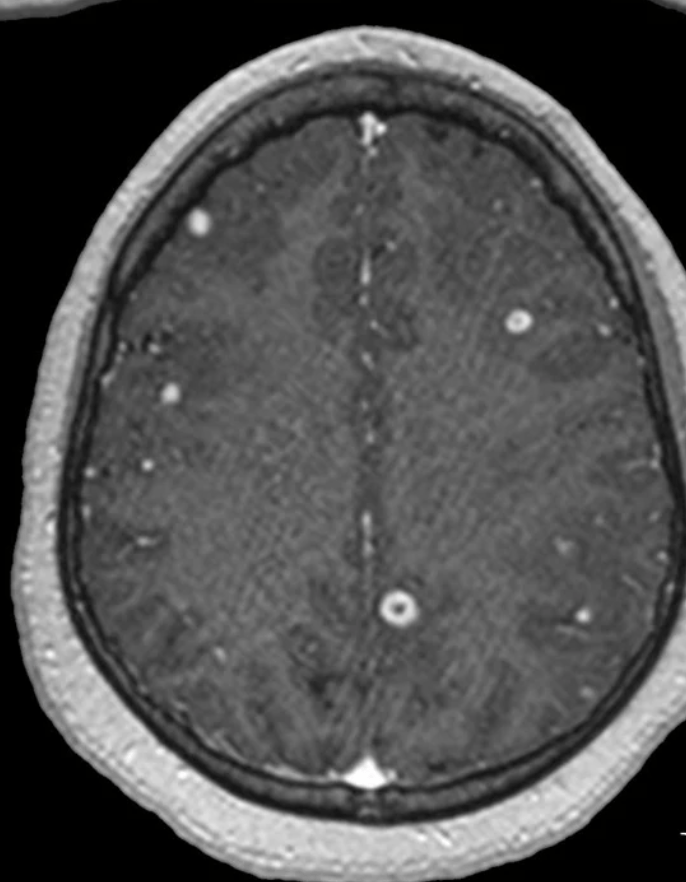

The commonest cause of this condition which can also cause meningitis

What is Herpes Simplex virus